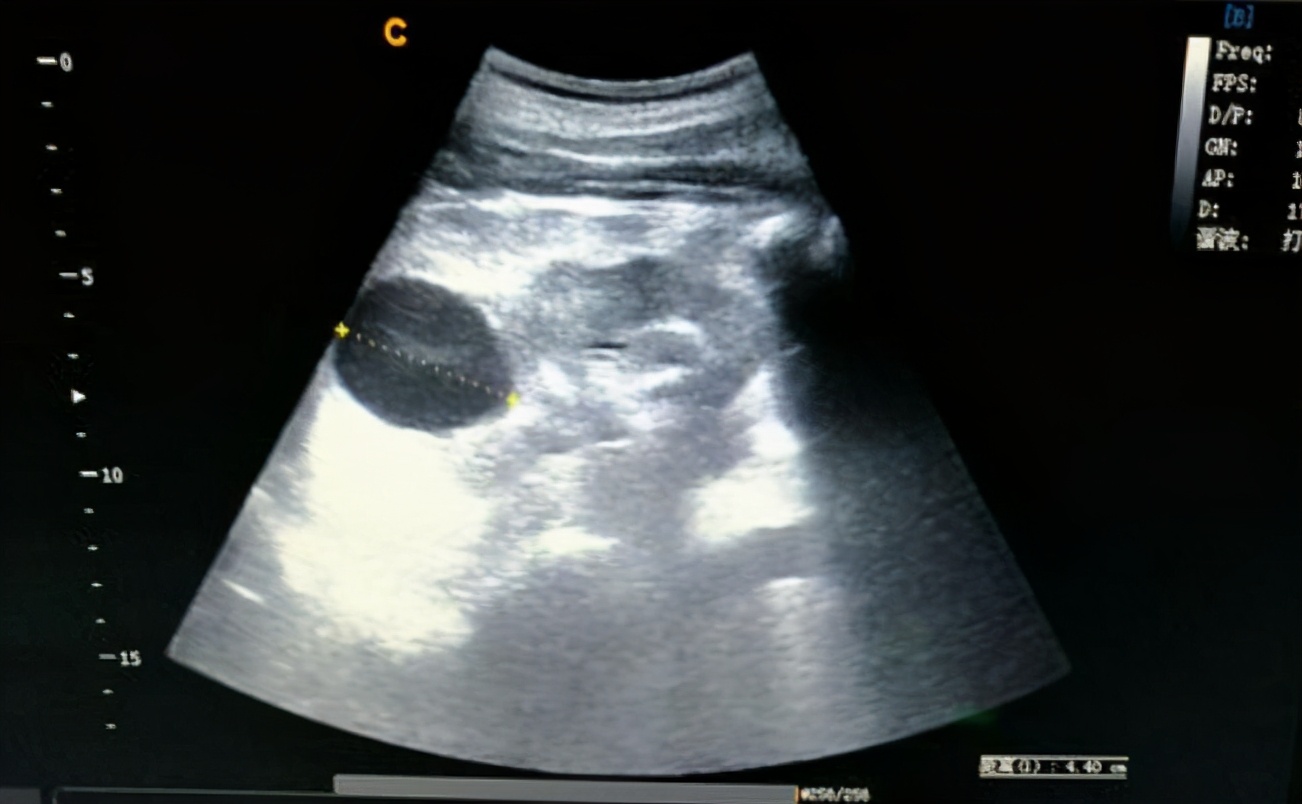

B超下肾囊肿典型表现为液性暗区

平时我们一般是通过健康体检或是查B超时候发现肾囊肿的。所以我们要检查自己是不是有肾囊肿,最简单、经济的方式是做个1)双肾B超,1cm以上的囊肿基本上都能发现,能大概了解囊肿位置、大小、数目等情况。 而当B超提示囊肿有分隔、钙化、或是实性成分时,需要进一步建议大家做 肾脏的增强CT或是核磁共振(MRI) 来排除肾恶性肿瘤性疾病。可以进一步判断囊肿的分型,并和肿瘤性病变做鉴别。3)怀疑是肾盂旁囊肿,或是考虑肾囊肿与集合系统(肾盂、输尿管)等关系密切时,需要做泌尿系CTU辅助诊断。而对于双肾囊肿,多发性肾囊肿或 有家族史的人群,推荐基因检测,排除遗传性肾囊性疾病。